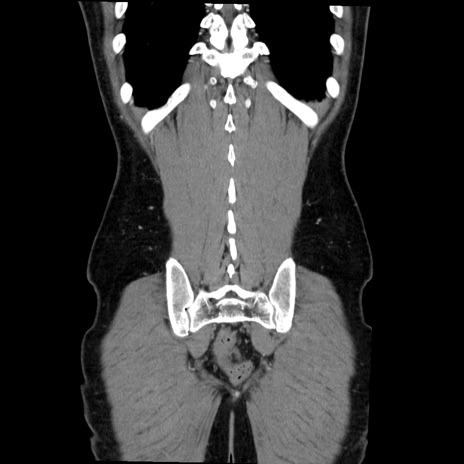

症例36(冠状断像)

【症例】20歳代 男性

【主訴】心窩部痛

【現病歴】今朝より上腹部痛あり。一旦軽快していたが再度出現したため救急要請。昨日夕に白身の魚を含む刺身を食べた。

【身体所見】BP 136/89mmHg、HR 74/min、BT 37.0℃、腹部:膨満、軟、心窩部に圧痛あり。反跳痛なし、筋性防御なし、腸雑音やや亢進あり。

【データ】WBC 17700、CRP 0.48